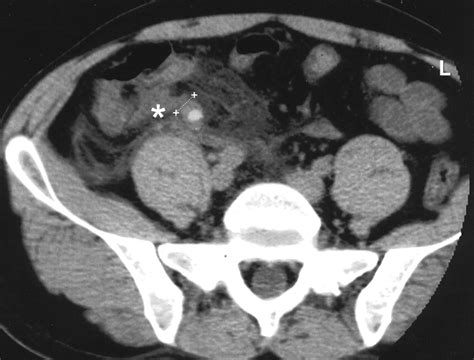

• Periappendiceal Fat Stranding: This appears as hazy, gray density surrounding the appendix, indicating that the inflammation has begun to spread into the surrounding fatty tissue.

• Extraluminal Fluid: The presence of free fluid around the appendix or in the pelvic cavity suggests that the appendix may be perforated or severely inflamed.

Once the radiologist identifies appendicitis on CT, the clinical path becomes much clearer. The scan helps the surgical team determine whether the condition is simple or complicated. A simple appendicitis is characterized by inflammation without rupture. A complicated appendicitis, on the other hand, might show signs of an abscess, perforation, or localized peritonitis.

These findings dictate the treatment plan. While an appendectomy (surgical removal) is the standard treatment for simple cases, complicated cases—such as those involving a large abscess—might initially be managed with intravenous antibiotics and, in some cases, percutaneous drainage guided by imaging, before a definitive surgery is performed later.